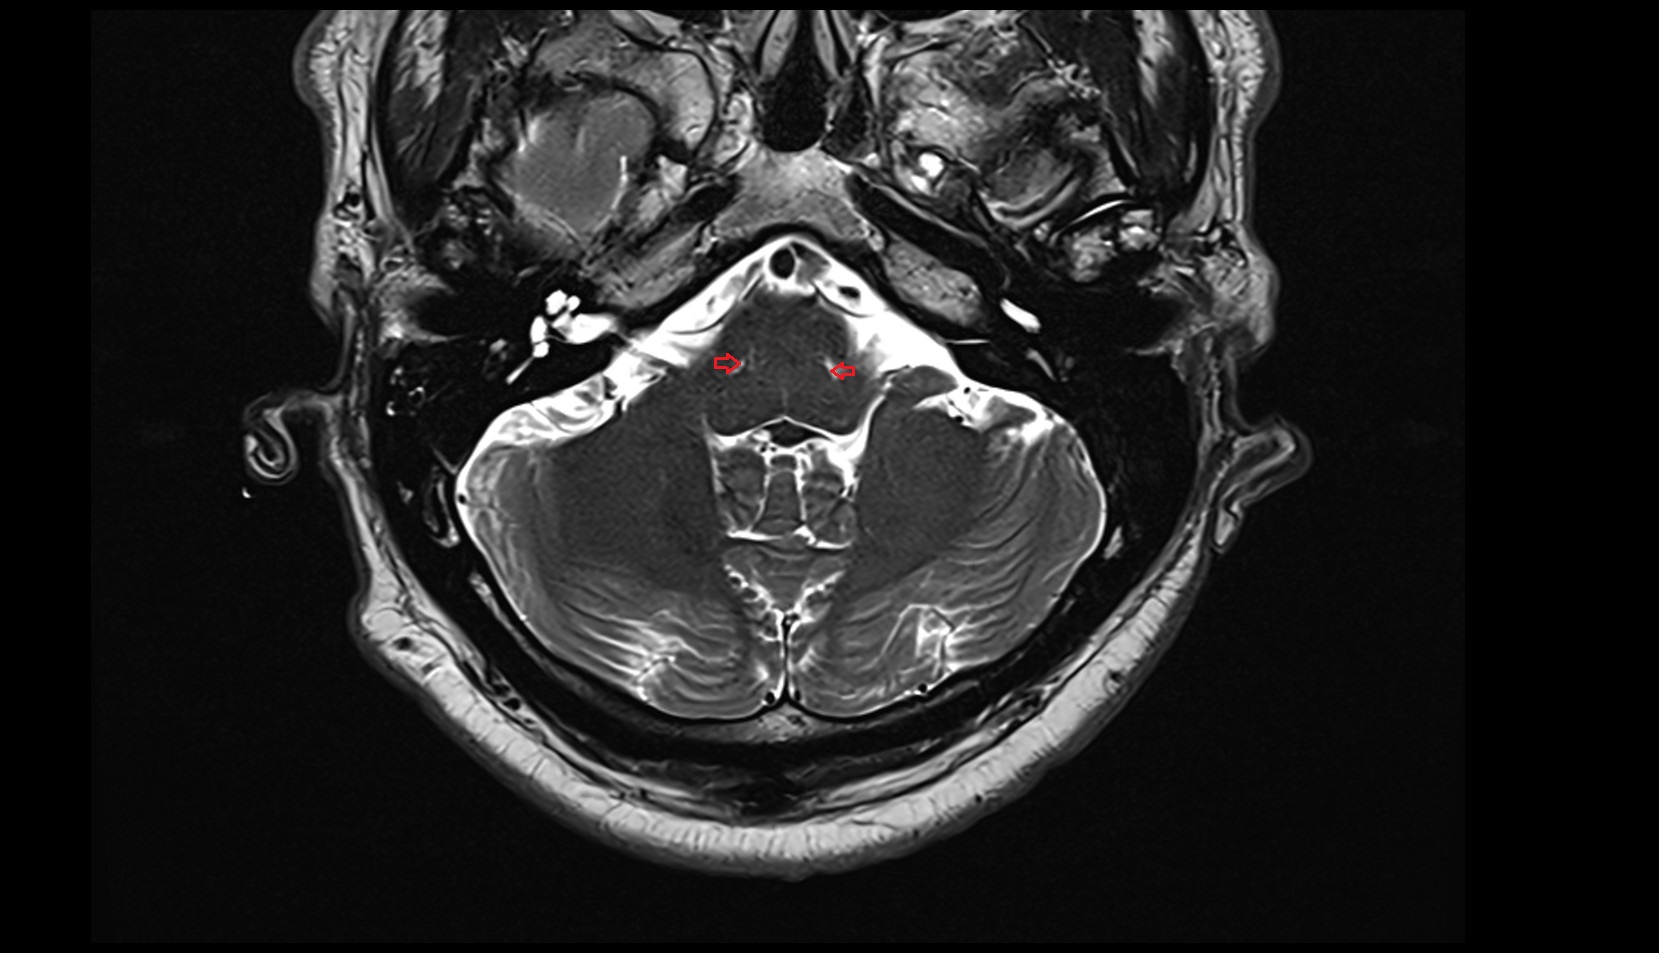

- Cerebellopontine cistern

- Lateral aperture of fourth ventricle (foramen of Luschka)